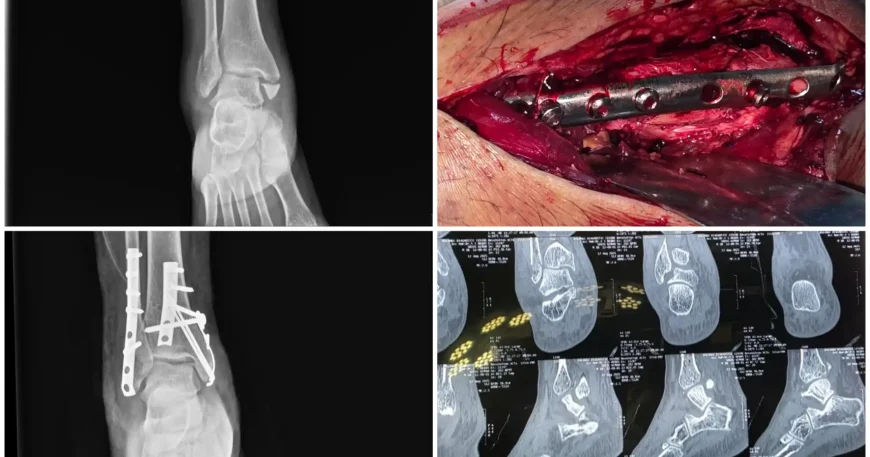

Clinical examination and imaging studies confirmed a Right Trimalleolar Ankle Fracture, involving:

-

Fibula (lateral malleolus)

-

Posterior malleolus

-

Medial malleolus

Such fractures disrupt ankle joint stability and require anatomical reduction for optimal recovery.

1️⃣ Open Reduction and Internal Fixation (ORIF)

Open reduction and internal fixation was performed for:

-

Fibula using plates and screws

-

Posterior malleolus using plates and screws

This ensured:

-

Accurate restoration of ankle alignment

-

Stable fixation of the lateral and posterior components

-

Proper joint congruity

2️⃣ Tension Band Wiring (TBW) for Medial Malleolus

The medial malleolus was stabilized using Tension Band Wiring (TBW) technique, which:

-

Converts tensile forces into compressive forces

-

Promotes stable bone healing

-

Provides strong fixation for small fracture fragments

The combined fixation approach restored full structural stability of the ankle joint.

Procedure Overview

| Condition | Right Trimalleolar Ankle Fracture |

|---|---|

| Main Procedure | Open Reduction and Internal Fixation (ORIF) |

| Fibula Fixation | Plates and Screws |

| Posterior Malleolus Fixation | Plates and Screws |

| Medial Malleolus Fixation | Tension Band Wiring (TBW) |